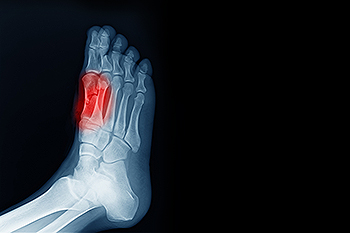

Sesamoiditis is a type of tendonitis that affects the two sesamoid bones that are located beneath the big toe joint. This condition occurs when the tendons surrounding these bones become inflamed, typically due to overuse or repetitive pressure. Symptoms of sesamoiditis include pain beneath the big toe, swelling, and tenderness, especially when walking, running, or bearing weight on the affected foot. You may also have trouble moving the toe or experience discomfort when wearing shoes. The primary cause of sesamoiditis includes activities that place repetitive pressure on the big toe, such as running, ballet, or jumping. Wearing ill-fitting shoes or high heels can also contribute to the condition. A podiatrist can help diagnose sesamoiditis through physical exams and imaging. Treatments may include rest, anti-inflammatory medications, custom orthotics to relieve pressure, or specific exercises to strengthen the foot. In severe cases, corticosteroid injections or surgery may be considered. If you have any of the above symtpoms, it is suggested that you schedule an appointment with a podiatrist.

Sesamoiditis

Sesamoiditis is a condition of the foot that affects the ball of the foot. It is more common in younger people than it is in older people. It can also occur with people who have begun a new exercise program, since their bodies are adjusting to the new physical regimen. Pain may also be caused by the inflammation of tendons surrounding the bones. It is important to seek treatment in its early stages because if you ignore the pain, this condition can lead to more serious problems such as severe irritation and bone fractures.

Causes of Sesamoiditis

Treatment for sesamoiditis is non-invasive and simple. Doctors may recommend a strict rest period where the patient forgoes most physical activity. This will help give the patient time to heal their feet through limited activity. For serious cases, it is best to speak with your doctor to determine a treatment option that will help your specific needs.